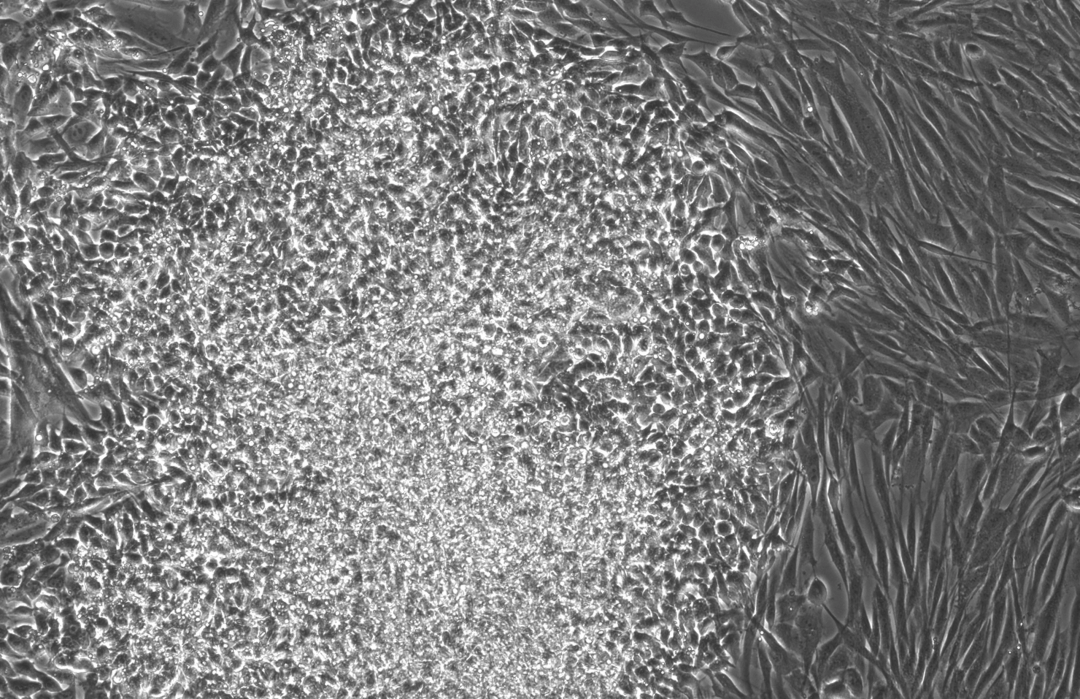

下面这三张图展示的是,OpenAI 设计的蛋白质能更高效地诱导干细胞重编程:

在这次的实验中,Retro 的团队利用人类成纤维细胞(来自皮肤和结缔组织)搭建了一个湿实验室筛选平台。

首先,他们使用标准的 OSKM 因子组合以及初步筛选中手动设计的 SOX2 变体,对平台进行了验证。

随后,他们让 GPT-4b micro 设计一组多样的「RetroSOX」序列。

筛选结果显示,模型给出的建议中超过 30% 的序列,在表达关键多能性标记物方面的表现优于野生型 SOX2,尽管它们与野生型的平均差异超过 100 个氨基酸。

作为对比,传统筛选的阳性率通常低于 10%。

下图显示,在初步筛选(Pilot)、RetroSOX 筛选和 RetroKLF 筛选中,表达早期多能性标记物 SSEA4(左柱)和晚期标记物 TRA-1-60(右柱)的细胞百分比。

可以看到,与效率极低(<0.1%)的常规方法相比,RetroKLF 显著提升了两种标记物的表达水平。

可以看到,将顶尖的 RetroSOX 和 RetroKLF 变体组合使用,带来了最大的性能提升。

在三次独立的实验中,成纤维细胞的早期(SSEA-4)和晚期(TRA-1-60, NANOG)标记物水平均出现急剧上升,且晚期标记物的出现时间比使用野生型 OSKM 组合方案提前了数天。

此外,研究团队在第 10 天通过碱性磷酸酶(AP)染色对 RetroSOX 和 RetroKLF 变体进行了验证。

结果显示,形成的细胞集落不仅表达晚期多能性标记物,还表现出强大的 AP 活性,这是细胞具备多能性的有力标志。

下面三张图中所有的结果共同证实了,研究团队已成功获得健康、且完全重编程的干细胞,从而也全面验证了重编程干细胞的健康与功能。

综上所述,高阳性率、深度的序列编辑、标记物的提前出现以及 AP 阳性集落的形成,这些早期证据共同表明,AI 指导的蛋白质设计能够极大地推动干细胞重编程研究的进程。